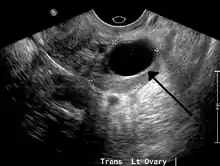

Transvaginal ultrasonography of a hemorrhagic ovarian cyst, probably originating from a corpus luteum cyst. The coagulating blood gives the content a cobweb-like appearance.